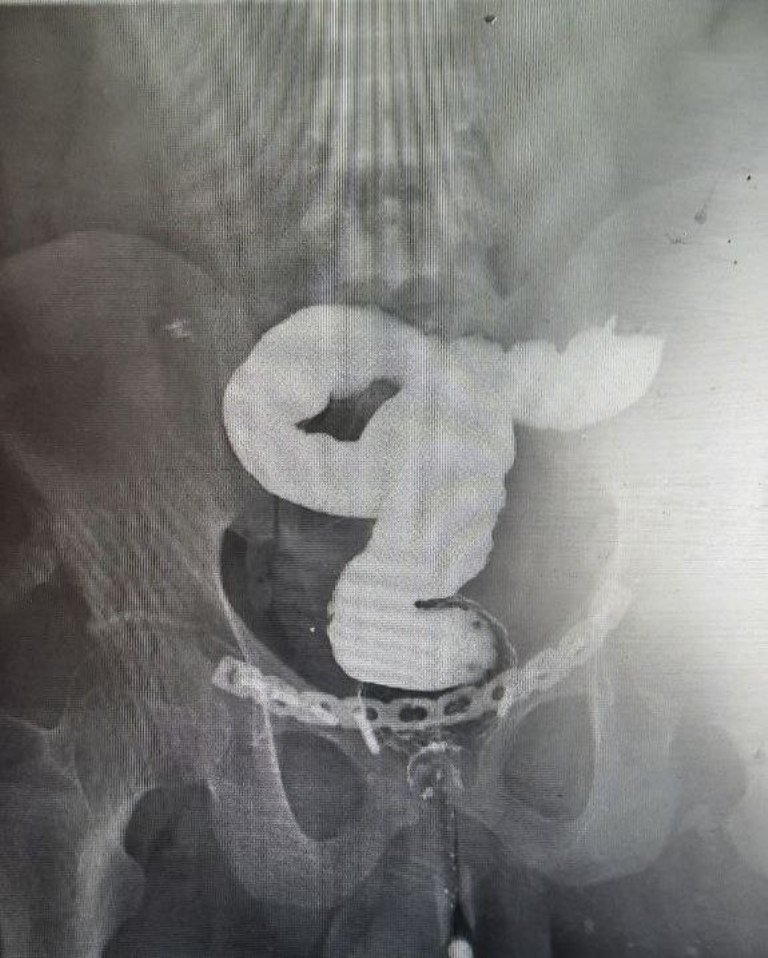

Во время строительных работ на 25-летнего каширянина упала железобетонная плита. Молодой человек был экстренно доставлен в больницу городского округа Кашира с множественными переломами тазовых костей, в том числе крестца, лучевой кости и вывихом локтевого сустава. Помимо этого медики выявили у пациента разрыв кишечника и других органов брюшиной полости. Было принято решение о проведении экстренной операции. Как сообщили в областном Минздраве, первым делом при помощи аппарата наружной фиксации были зафиксированы переломы, удалена часть поврежденного кишечника с выведением двух стом. Далее врачи выполнили рассечение множественных спаек брюшной полости, образовавшихся вследствие тяжелой травмы внутренних органов, провели реконструктивную операцию по восстановлению кишечника и другие восстанавливающие действия.

К счастью, операция, которая длилась более 4 часов, прошла успешно. Сейчас пациент чувствует себя хорошо и уже выписан на амбулаторное лечение.